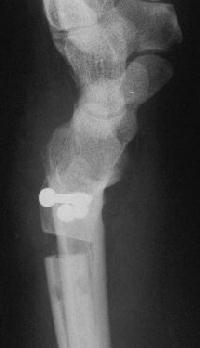

Case 3. Adult bilateral congenital Madelung's deformity with pain and extensor tendinitis, treated with the Sauve Kapandji (Lauenstein) procedure: segmental distal ulnar ostectomy and distal radioulnar joint fusion.

Right side, postop.